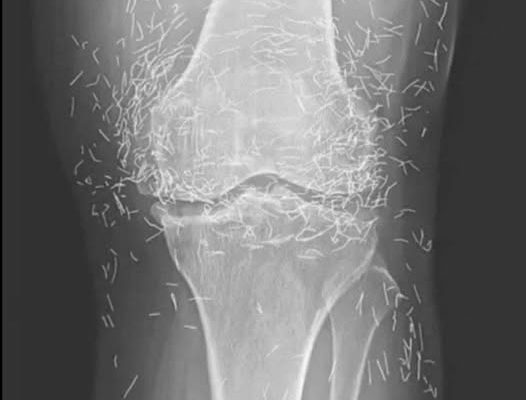

Years later, when doctors took X-rays to evaluate her knee condition, they weren’t prepared for what appeared on the images. Her knees were filled with dozens of bright, metallic flecks — tiny needles embedded deep within the joint area.

The findings were later documented in a case published by the New England Journal of Medicine.